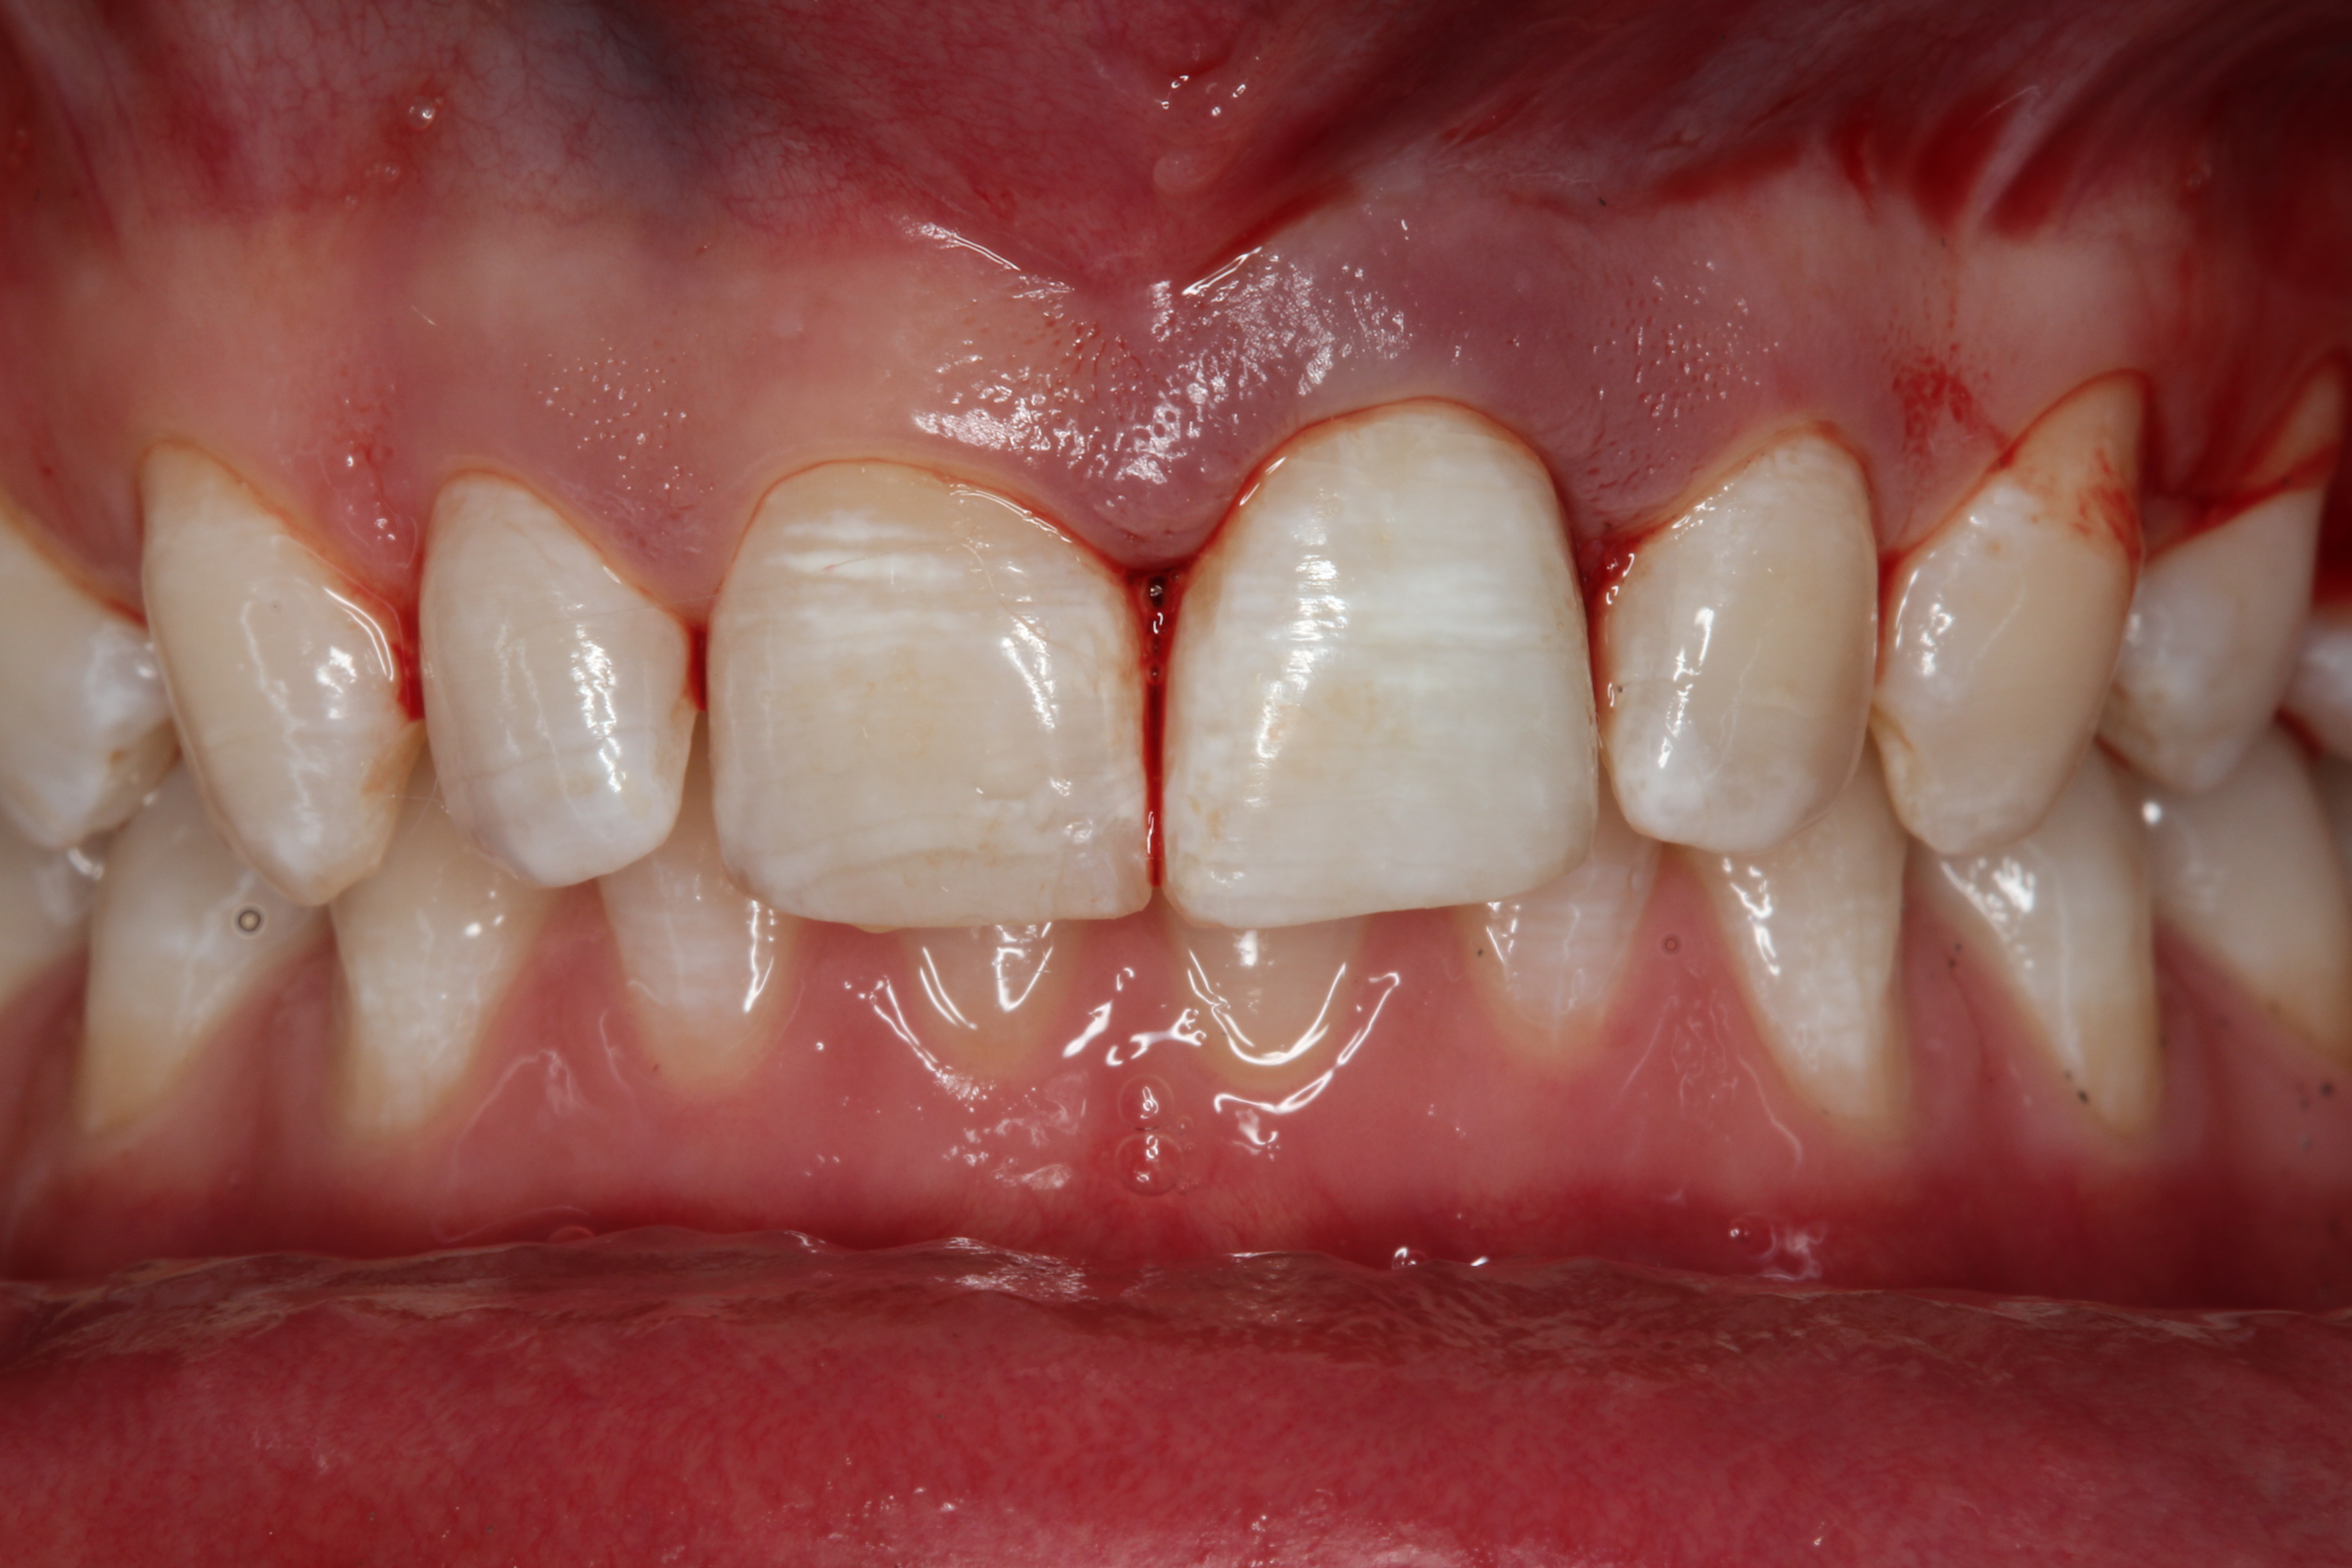

Fig 2. Preoperative photograph after trauma.

Figure 2

A young man presented with a fractured maxillary left-central incisor on a Monday morning after a Saturday evening discussion that did not end well (Figure 1). Visual oral examination and palpation of the structures revealed mobility of 3+, pain on palpation and percussion, a thick soft-tissue profile, and a low lip line. Gingival zeniths were irregular, there was a class II division 2 deep bite, and the periodontium was healthy overall (Figure 2 through Figure 4). Radiographs requested at the time of the initial visit were periapicals, panoramic, and CBCT images (Figure 5 and Figure 6). After all images and information were reviewed and the extent of his injury was discussed, the patient was presented with the following options: removable prosthetics, fixed partial denture, extract and do nothing, or extract and place a dental implant with bone augmentation.